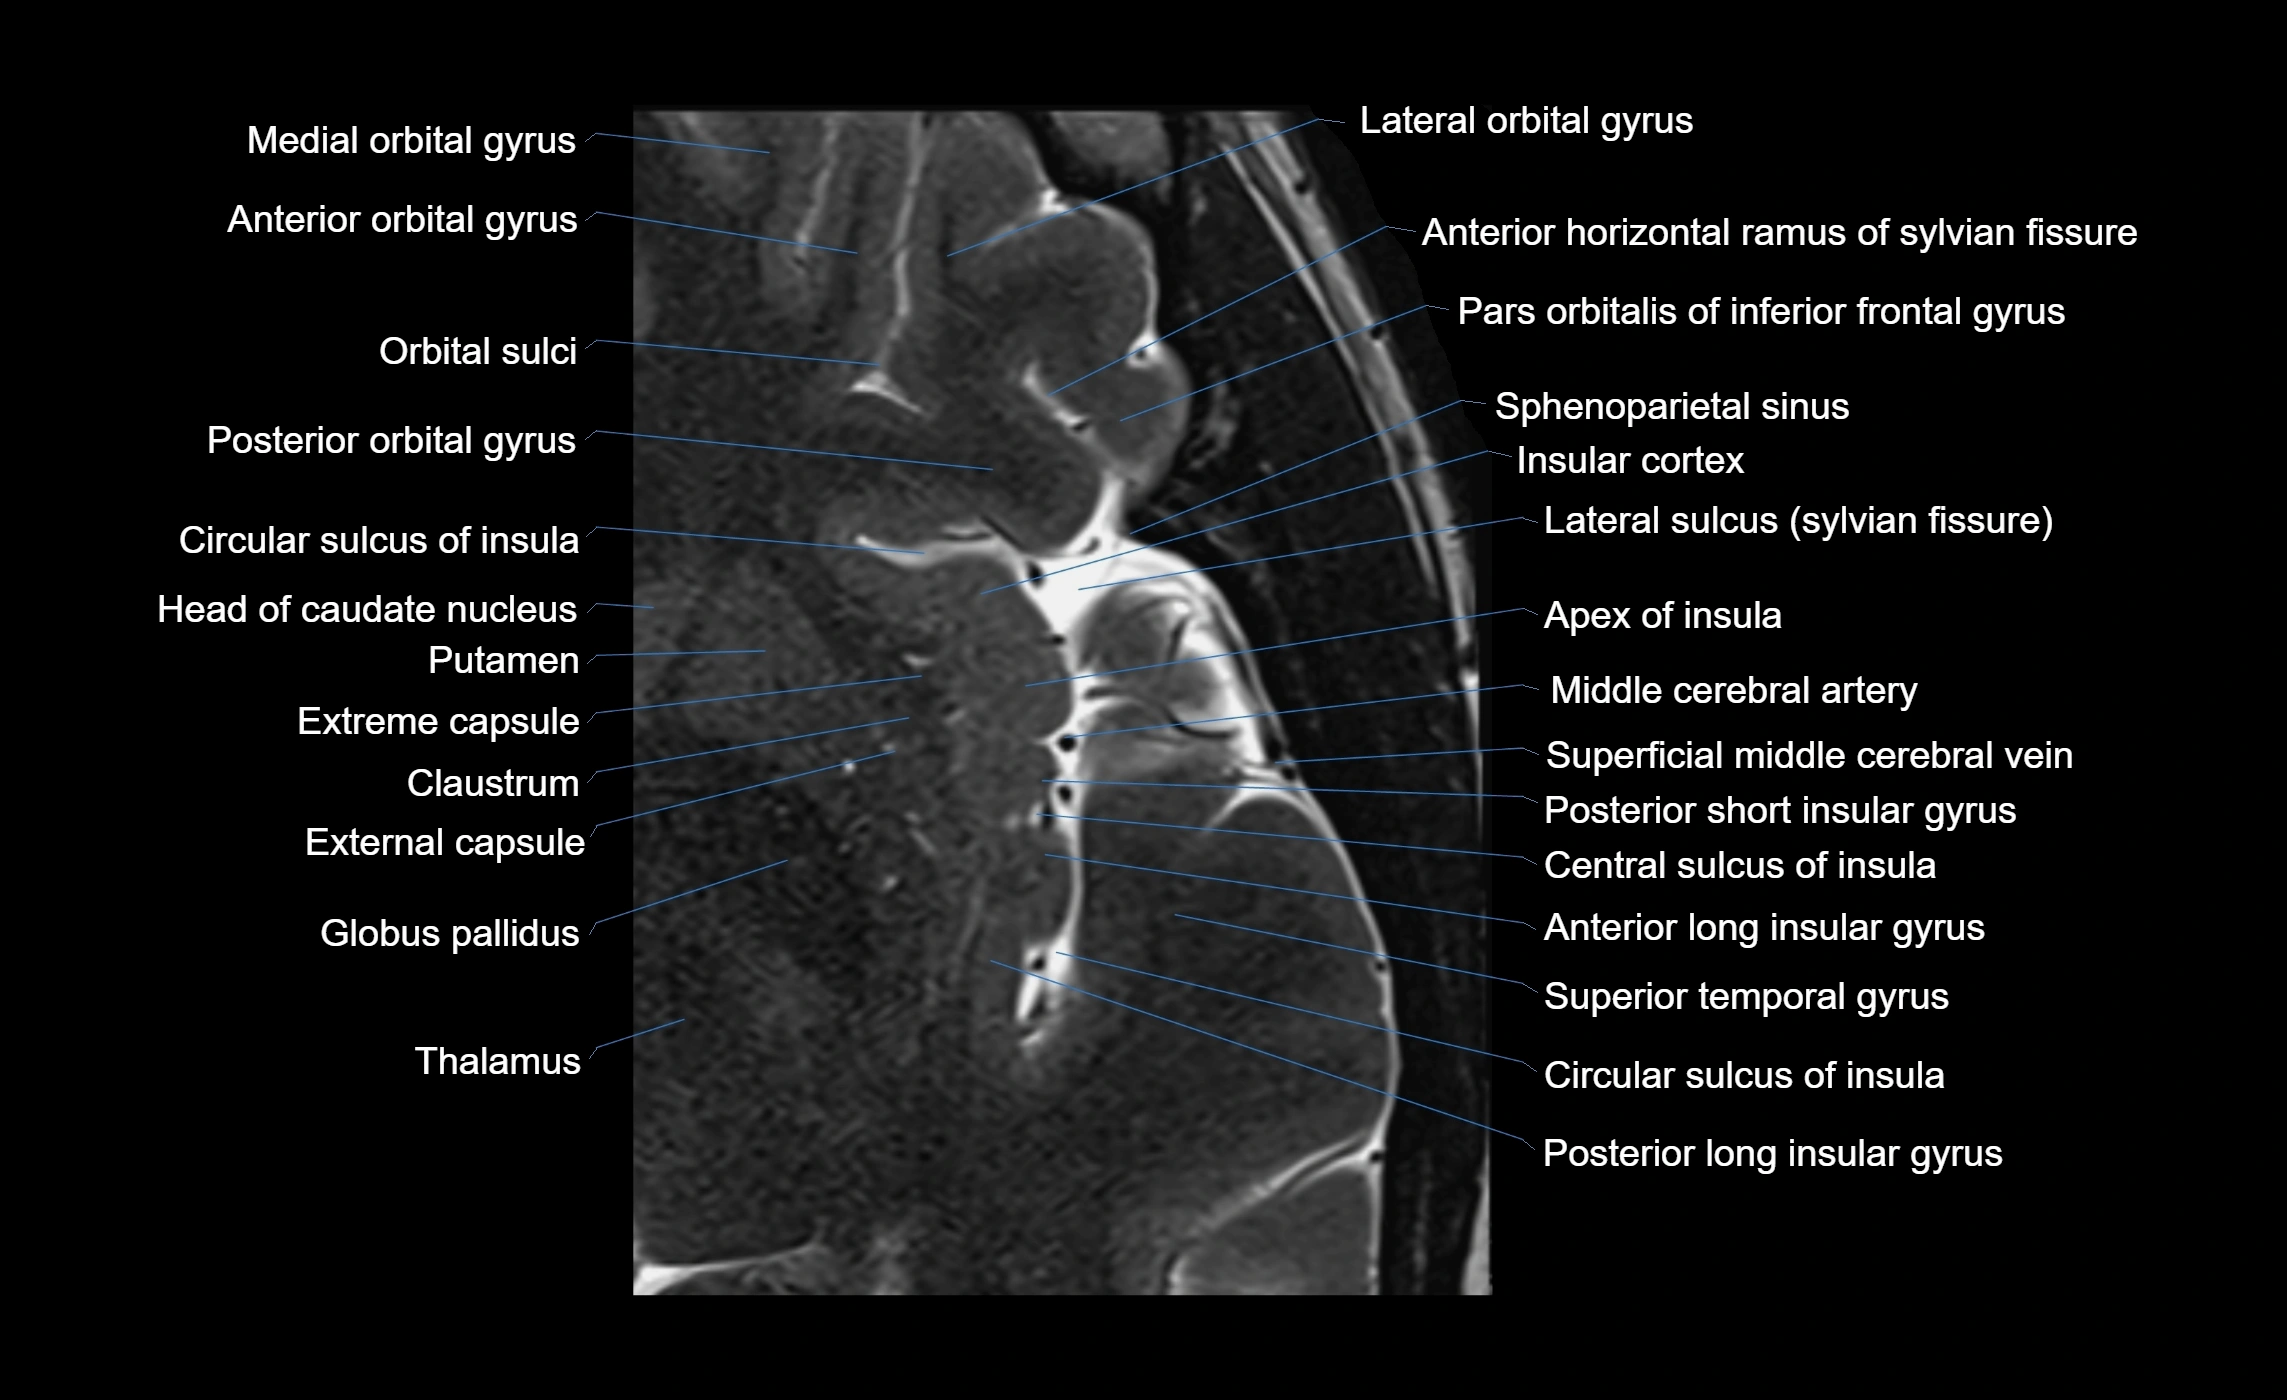

The anterior ascending ramus of the Sylvian fissure is a significant anatomical landmark in the lateral surface of the cerebral hemisphere. It represents one of the key branches of the Sylvian fissure (also known as the lateral sulcus) and plays an essential role in demarcating the boundaries between important cortical regions, notably within the frontal and parietal lobes. Understanding its anatomy and imaging appearance is crucial in neuroradiology, neurosurgery, and neuroanatomy for accurate localization and identification of adjacent brain structures.

• The anterior ascending ramus is a short, superiorly oriented branch that arises from the main stem of the Sylvian fissure.

• It projects upward (anteriorly and slightly dorsally) from the lateral sulcus into the inferior frontal gyrus.

• This ramus separates the pars opercularis (opercular part) from the pars triangularis (triangular part) of the inferior frontal gyrus.

• The anterior ascending ramus marks the boundary between Broca's area and adjacent cortical areas in the dominant hemisphere.

MRI Appearance

• T1-weighted imaging:

• The Sylvian fissure and its anterior ascending ramus appear as low-signal intensity (dark) CSF-filled clefts between the gyri.

• Clear demarcation between adjacent gray and white matter.

• T2-weighted imaging:

• The fissure, including the anterior ascending ramus, is hyperintense (bright) due to CSF signal.

• Better visualization of the separation between opercular and triangular parts of the inferior frontal gyrus.

• FLAIR imaging:

• The ramus is visualized as a linear dark space (suppressed CSF signal) between the surrounding cortex.

• Adjacent cortical and subcortical abnormalities (e.g., edema or gliosis) can be assessed relative to the ramus.

MRI images

image